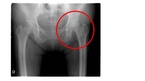

잦은 음주를 하는 회사원 A씨는 언제부턴가 엉덩이와 허리에 자주 통증을 느꼈다. 특히 맨 바닥에 오래 앉아 있거나 양반다리를 할 경우에 사타구니 부위의 통증이 심해져 의자가 없이는 생활하기 힘들 정도였다. 허리와 엉덩이 부위의 통증이 심해 혹시 디스크가 아닐